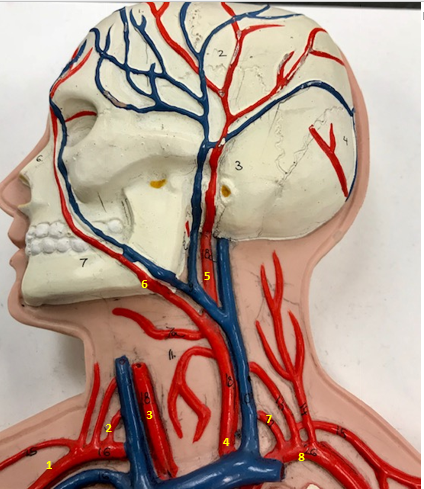

Right subclavian artery

Name #1

Supplies blood to right arm and shoulder

Function of right subclavian artery (1)

Right vertebral artery

Name #2

Supplies blood to brain and spinal cord

Function of right vertebral artery (2)

Right common carotid artery

Name #3

Supplies blood to right neck and head

Function of right common carotid artery (3)

Left common carotid artery

Name #4

Supplies blood to left neck and head

Function of left common carotid artery (4)

Left external carotid artery

Name #5

Supplies blood to face neck and skull

Function left external carotid artery (5)

Left facial artery

Name #6

Supplies blood to face and neck

Function of left facial artery (6)

Left vertebral artery

Name #7

Supplies blood to brain and spinal cord

Function of left vertebral artery (7)

Left subclavian artery

Name #8

Supplies blood to left arm and shoulder

Function of left subclavian artery (8)